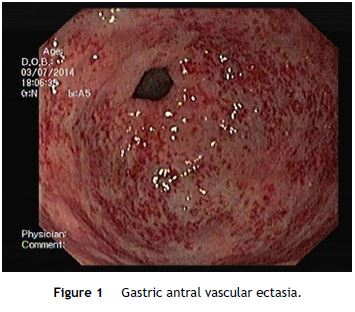

At oesophagogastroduodenoscopy (OGD), GAVE may appear as multiple longitudinal streaks that converge at the pyloric orifice, with a “watermelon” pattern (stripe type), or as multiple erythematous spots (diffuse or granular type).6 This last form occurring more frequently in patients with cirrhosis.6

An OGD was performed and revealed multiple erythematous spots in the antrum compatible with GAVE, diffuse type (Fig. 1), and mild portal hypertensive gastropathy, without active bleeding. There was no evidence of esophageal or gastric varices. GAVE was treated with APC without complications (Fig. 2). A colonoscopy with ileoscopy was also performed, but it was negative for blood or hemorrhagic lesions. Her hemoglobin levels remained stable and the patient was discharged and started on propranolol (for portal hypertensive gastropathy), with a target of 55 beats per minute, 40 mg of pantoprazole every 24 h and performed iron intravenous supplementation in ambulatory.